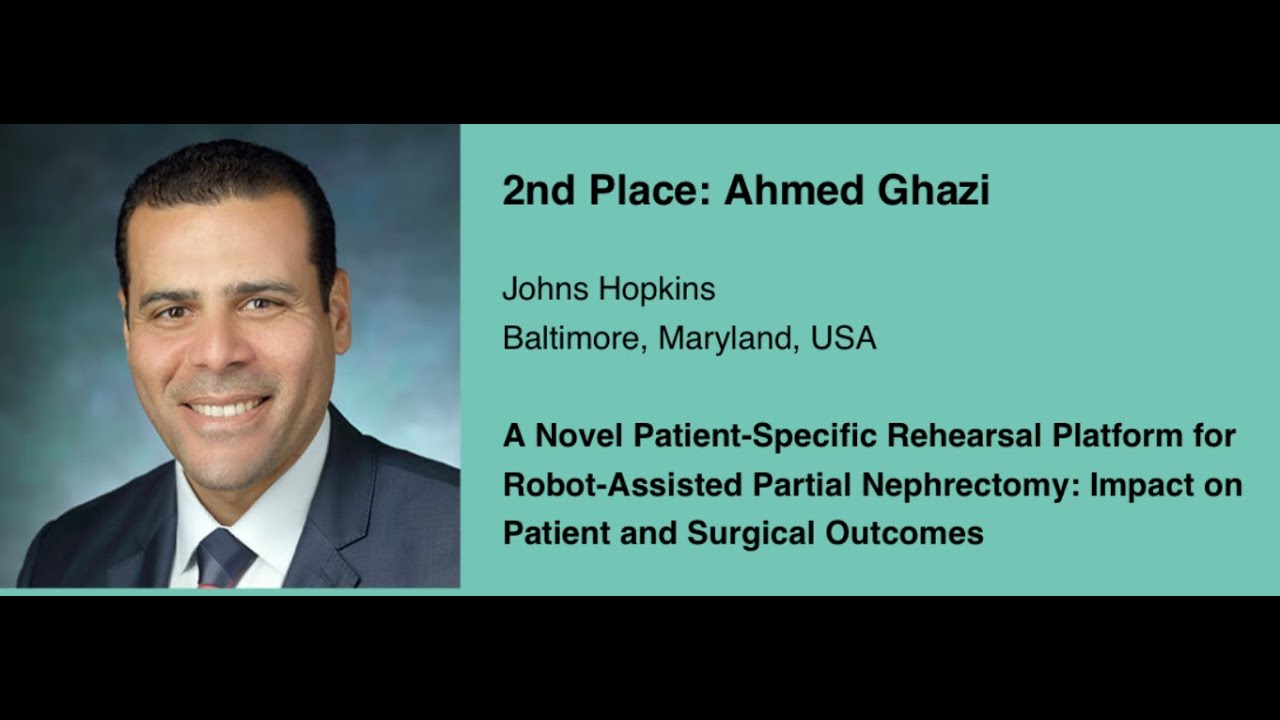

2nd Place: #274- Dr. A. Ghazi: A Novel Patient-Specific Rehearsal Platform for Robot Assisted Partial Nephrectomy

KS Awards, Robotics, Surgeon ';